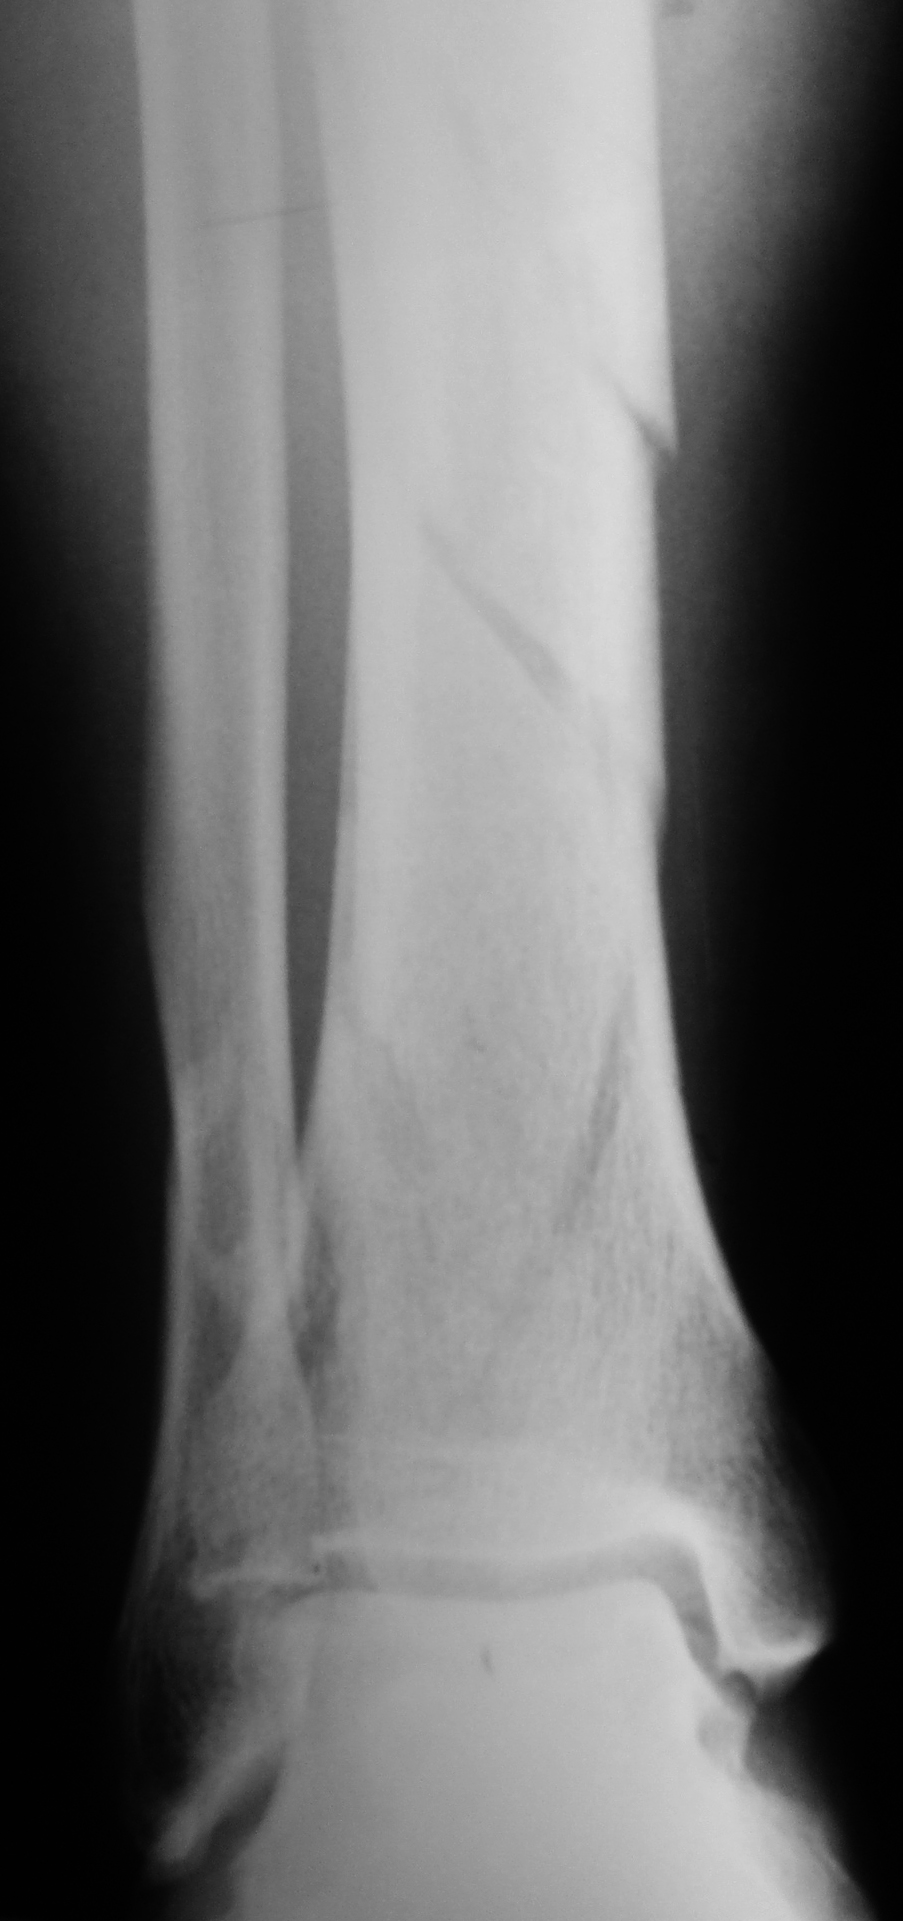

Osteosíntesis mini-invasiva con placas bloqueadas en fracturas metafisarias distales de tibia. Resultados clínico-funcionales. [Minimally invasive plate osteosynthesis in distal metaphyseal fractures of tibia. Comparison of results between fractures AO 43A and AO 43C.]